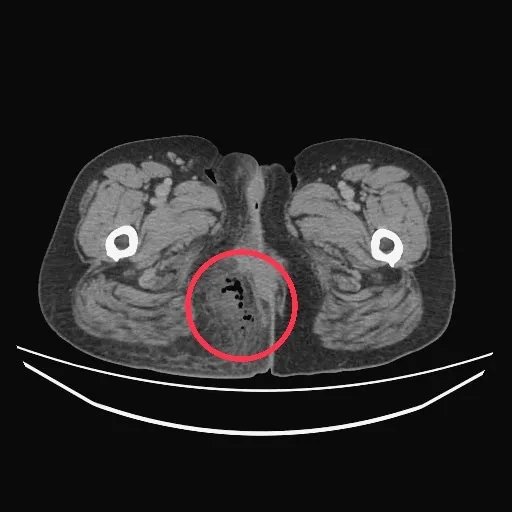

阿秀因魚刺卡進肛門組織,導致周邊發炎潰爛。台中醫院提供

台中醫院消化外科主任曾旭弘醫師表示,由於患者並未提到飲食的問題,所以醫療團隊一時也未往異物侵入的方向去思考,但由於患者的肛門組織發炎相當嚴重,需緊急施作清創手術,他是在切開患部時,才找到讓阿秀痛不欲生的「罪魁禍首」,一根長超過3公分的魚刺,刺入肛門右側組織,導致組織發炎壞死。

曾旭弘表示,由於需清除女子肛門附近的壞死組織,因此開了一個約6公分大小的切口,考慮到如此大的傷口照顧不易,若讓患者正常飲食與排便,恐怕肛門的傷口不易癒合,在經過專業的評估意見,再加上「全靜脈營養醫學」小組與「高壓氧治療」團隊等院內的醫療資源整合後,決定先讓患者施打「全靜脈營養針」,並輔以「高壓氧」來縮小手術傷口。